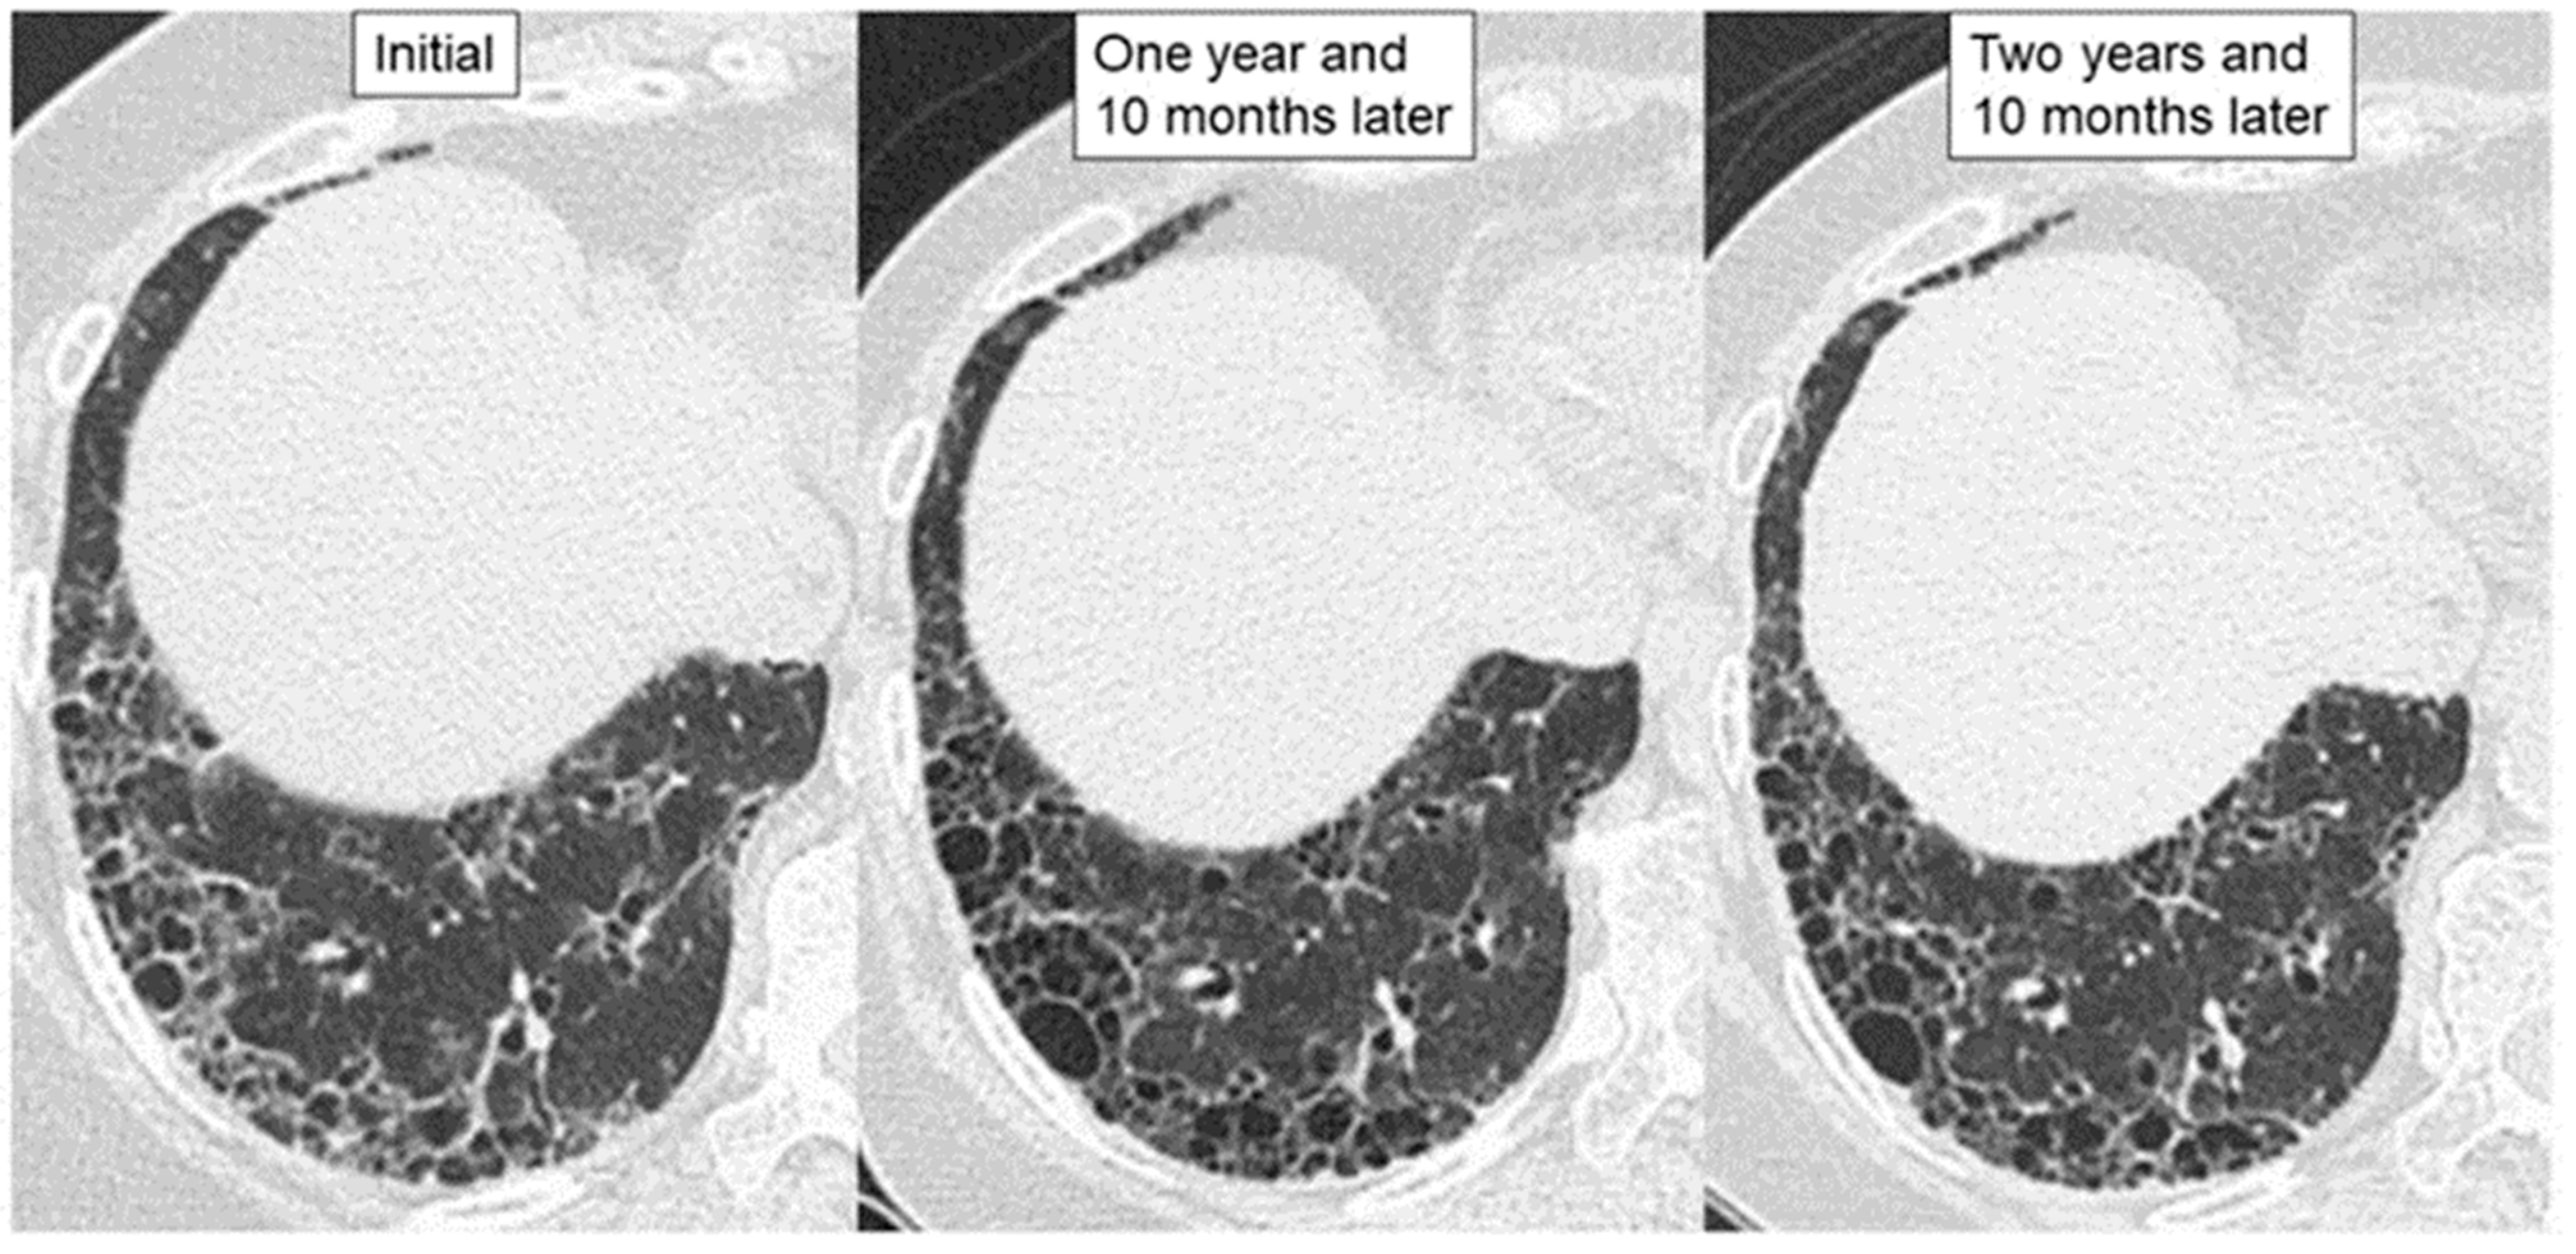

Figure 3.

High-resolution computed tomographic images of a patient with a stable course of MPA-ILD with UIP pattern for less than 3 years. The patient received anti-inflammatory therapies, after which wall thickening in the areas of honeycombing had improved, and the fibrotic lesion did not extend without requiring administration of an anti-fibrotic agent.